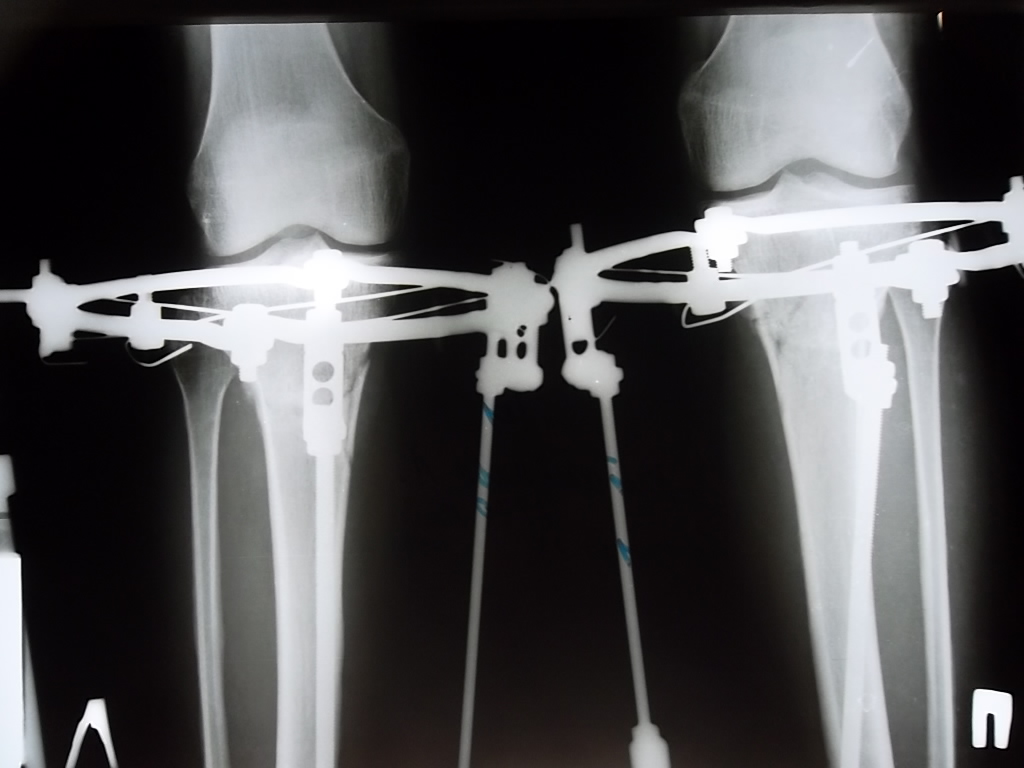

Контрольный рентген-снимок сделали, Николай Николаевич сказал, что все ок у нас.

Ягодуля, вчера нам убрали по одному штырю снаружи, слева и справа. Сегодня уберут оставшиеся штыри полностью, т.е. будем ходить только с кольцами. Не будет никакой опоры, придерживать ничего не будет. Страшновато. 094f316296.gif Если подробно, то вот так.

Дата операции 06.03.2013г.

Дата снятия аппаратов 18.06.2013г.

Срок лечения 102 дня.

рентгеновские снимки за 2 недели до снятия аппаратов.